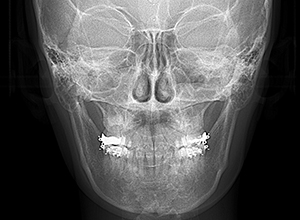

動的治療終了時

X-Ray